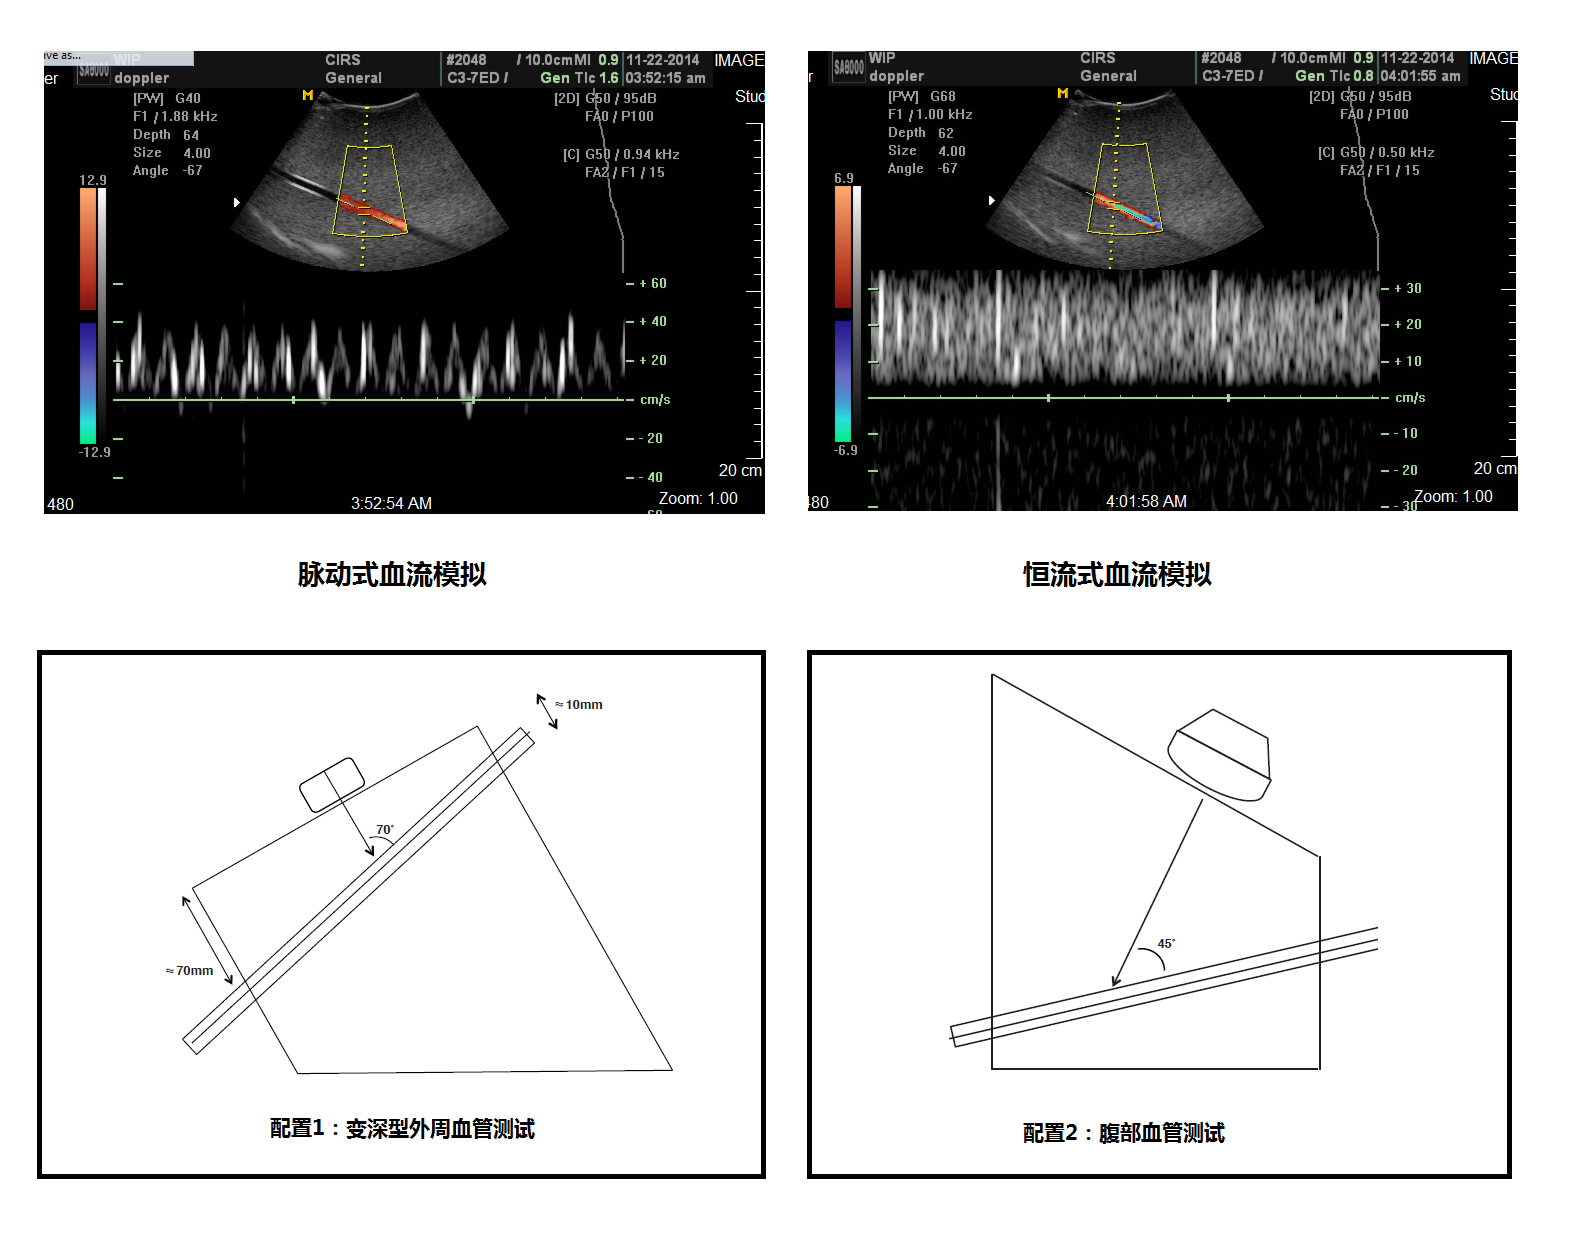

模擬機(jī)包含一個(gè)仿真流量模體,一條模擬血管的超聲配用導(dǎo)管斜插在模體之中。模體頂部和底部均設(shè)有掃描表面,提供不同深度和角度的應(yīng)用需要。這樣的設(shè)計(jì)充分發(fā)揮模體的靈活性來測(cè)試皮表掃描和深度腹腔血管的掃描的需求。

3.脈沖流和均速流兩種選擇

5.漸變深度,表層和腹腔血管模擬

模塊1 內(nèi)置血管1條,夾角45°70°,血管內(nèi)徑3/16in,模擬腹部血管,外周血管